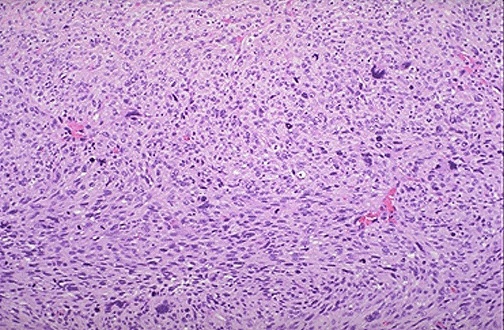

Image 5.2

This is the low power microscopic appearance. Describe it.